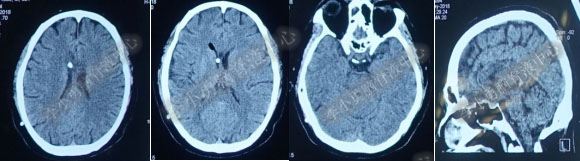

第1次内镜术后330余天即11个月(2017年4月),又开始出现头晕症状并逐渐加重。2017年6月13日(第1次内镜术后367天),行头部MRI(图-4)检查显示全脑室系统扩大。

图-4:2017年6月13日头部MRI

2017年6月19日(第1次内镜术后404天即一年零39天),因原症状加重,第2次住入该院。2017年6月20日(住院第2天),复查头部MRI(图-5)。

图-5:2017年6月20日头部MRI